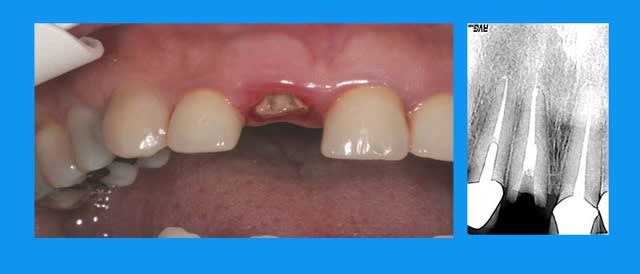

curieux de voir que le dépassement a suivi la dent... serait un instrument cassé?

Dépassement dt5hca - Eugenol

aucune idée

la patiente a en bouche des ceramiques faites depuis plus de 15 ans(made in USA)avec les traitements s'y référents

seule la 11 a cassée(due au deplacement de l'antagoniste? peut être,sans doute)

je ne me suis pas acharnée à retirer le cône noyé ds la pâte(acryl? ou thermafill mais cela existait il à l'epoque?) vu l'absence d'image apicale et.... le fait que je n'y suis pas arrivée:)

tort? raison?

on verra mais à un an 1/2(IC et prov posés en nov 2005) pas gd chose ne se passe

10/07/2008 à 15h50

oui, c'est visiblement bien toléré, juste frustrant de ne pas savoir, filet de ciment? cone? en tous cas, ça suit la dent.